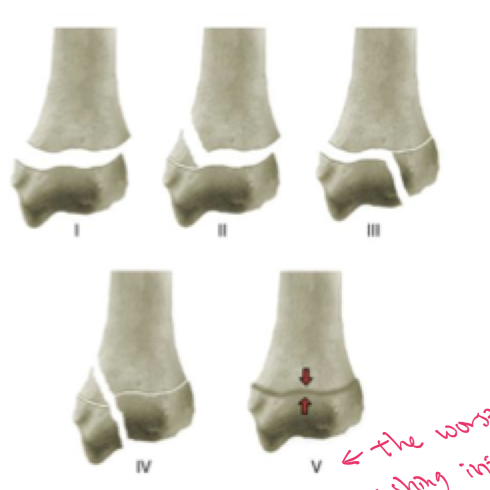

The physis that is most susceptible to premature closure secondary to compaction is which one?

Distal ulnar physis

w/ this one, we will often see a SH-V fracture

SALTER

S → straight across

A → above

L → below

T → through

ER → Crush